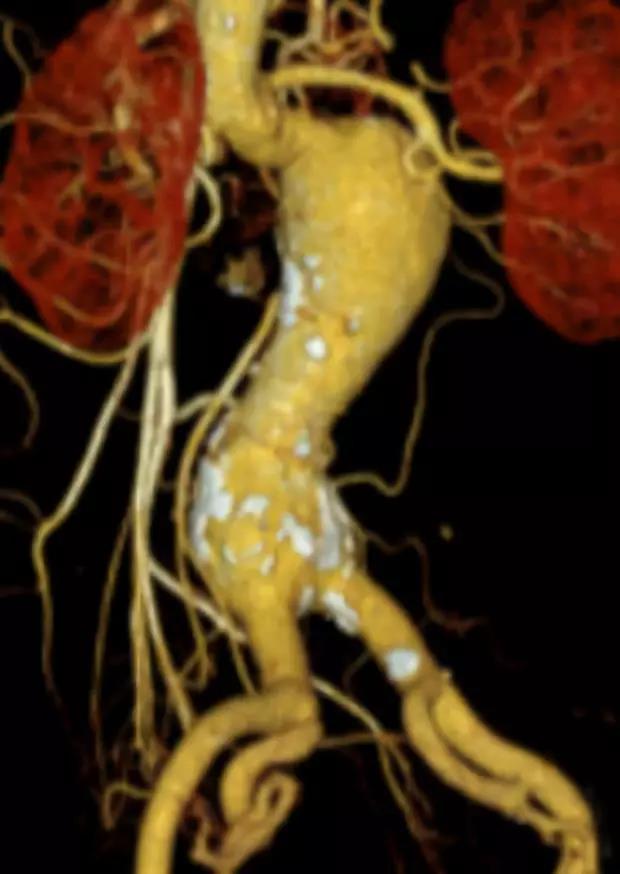

此次研究,纳入腹主动脉瘤的最大直径为85mm,平均直径为50.78mm;最短瘤颈长度为11mm,平均长度为31.34mm;最大肾下成角为74.6度,平均角度为32.48度。从动脉瘤最大直径变化来看,经过腹主动脉腔内治疗后,在出院前和术后6个月都有所减小。 在此次研究中,先健Yuranos™新一代腹主动脉覆膜支架系统临床试验初步展现了优秀的临床试验结果,其30天内MAE发生率低,安全性得以验证;而且由于该产品的柔顺性有较大提升,输送器直径减小,对于短瘤颈和角度大的病例是更好的选择。 入组病例展示: 病例一:男性,年龄69岁,既往高血压,糖尿病病史。术前腹主动脉瘤直径67.3mm,近端瘤颈长度23.2mm,近端锚定区直径21.2mm,肾下成角60.5度。 术中从右侧股动脉穿刺,选用先健型号为AB-2412-50-120的主体支架,支架近端定位于右肾动脉开口处,后释放打开裸支架,并向下释放主体短分支,左侧输送进入先健髂动脉延长支架IE-1416-100,并释放,保留左侧髂内动脉。接着释放主体长分支,右侧输送进入先健髂动脉延长支架IE-1424-80,并释放,保留右侧髂内动脉。 手术顺利,无内漏,持续时间1小时10分钟。术后CTA检查,支架形态良好,无内漏。详见下图: 术前影像 术中影像 出院前影像 术后6个月影像 术后1年影像 病例二:女性,年龄72岁,既往高血压,静脉曲张病史。术前腹主动脉瘤直径48.81mm,近端瘤颈长度16.15mm,近端锚定区直径18.43mm,肾下成角66度。 术中从右侧股动脉穿刺,选用先健型号为AB-2412-50-140的主体支架,支架近端定位于右肾动脉开口处,后释放打开裸支架,并向下释放主体短分支,左侧输送进入先健髂动脉延长支架IE-1414-120,并释放,保留左侧髂内动脉。接着释放主体长分支,右侧输送进入先健髂动脉延长支架IE-1414-80,并释放,保留右侧髂内动脉。

手术顺利,无内漏,持续时间1小时10分钟。术后CTA检查,支架形态良好,无内漏。详见下图: